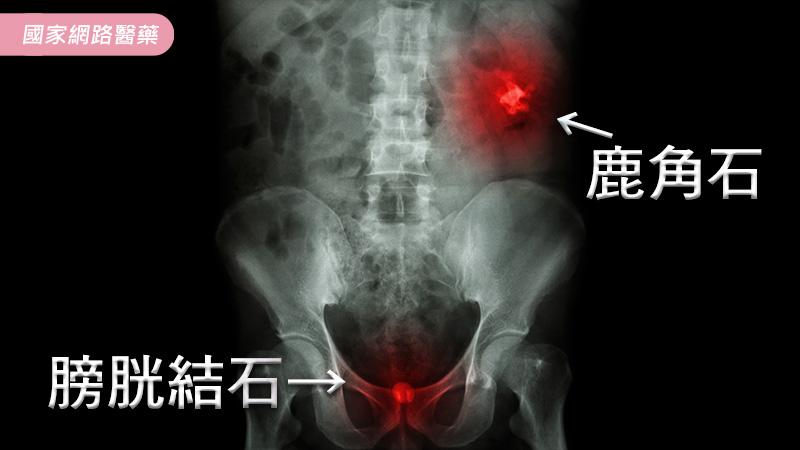

在臨床上結石的症狀,可分為1.無感:初期輕微的結石病患是無感的,病人甚至不知道自己罹患結石。有些病患可能完全沒有症狀,但是二側的腎臟可能已經完全被結石佔滿,即俗稱的鹿角石。雖然沒有明顯症狀,但因為長期排泄尿液的情況不佳,腎功能逐漸喪失中。2.有感:結石掉落,卡住輸尿管,造成尿液減少或急性疼痛的發生,常見的急性疼痛發生在腰部(腎臟的位置),合併血尿問題。泌尿管的結石疼痛與一般肌肉拉傷造成的疼痛最大的差異,就是泌尿管結石的疼痛,不會因為姿勢的改變而減緩。若曾經罹患結石的病患,應每一年定期追蹤檢查,因為結石的好發率是非常高的(曾經罹患結石的病患,五年內約有50%的病患,會因結石疼痛而再度就診)。

尿酸類結石,是因為身體對嘌呤(普林、Purine)的代謝出現問題,除了要多攝取水分外,在食物攝取上,應避免過多高嘌呤食物(例如:火鍋湯、海鮮、動物內臟等)。感染性結石,即上述的鹿角石,除了應多攝取水分外,醫師亦會給予酸化尿液的藥物,並建議病患可以多攝取蔓越莓,並多注意慢性感染的問題。